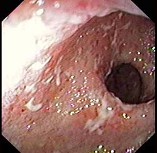

男,70岁,右下腹胀,腹痛,腹泻,影像检查如图,最可能的诊断是( )

A:结肠克隆恩病

B:结肠癌

C:结肠套叠

D:结肠结核

E:结肠淋巴瘤